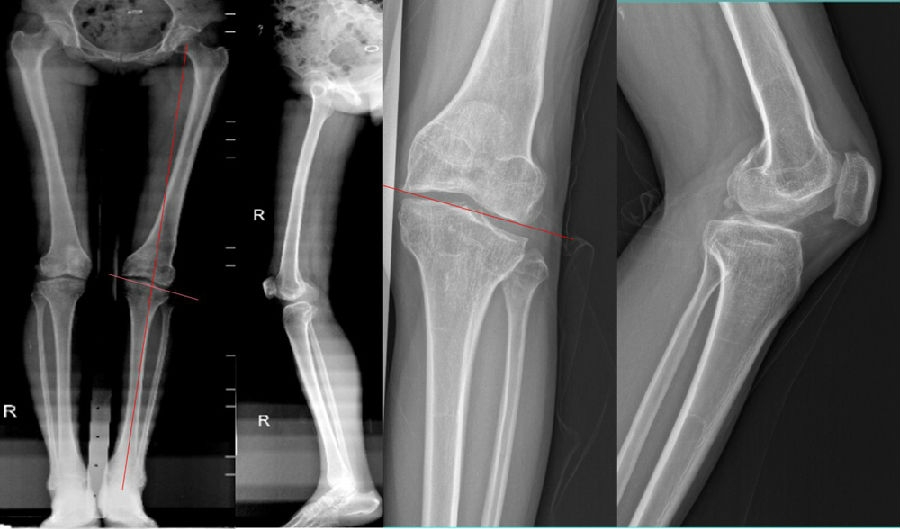

术前X线片

术前X线显示:

胫骨近端内侧角(MPTA):100°

股骨远端外侧角(LDFA):102°

关节线夹角(JLCA):3°

股骨远端后倾角(PDFA):85°

胫骨近端后倾角(PPTA):83°

术前MR